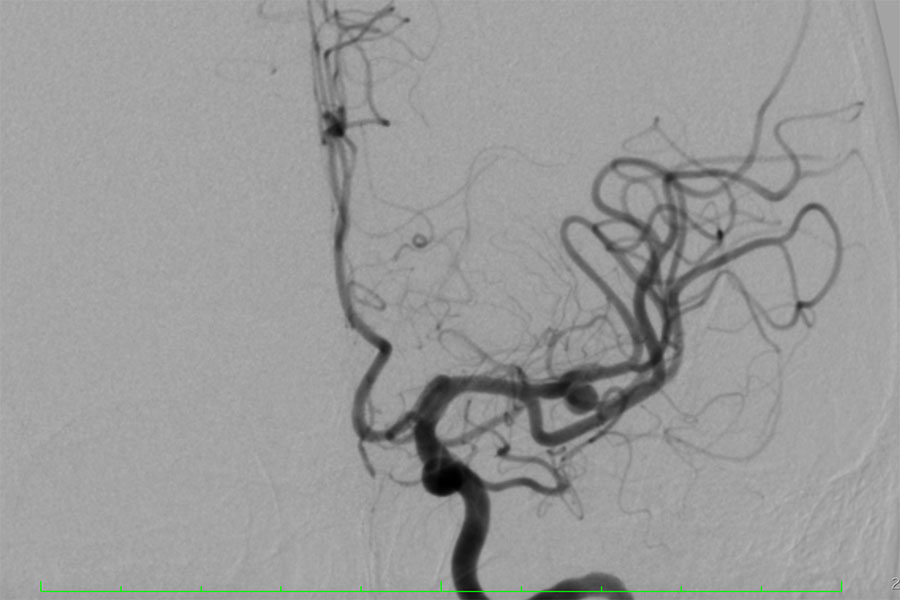

Գլխուղեղի զարկերակային անևրիզմայի ներանոթային բուժում

«Արմենիա» ՀԲԿ դիմած 48 տարեկան երիտասարդ կնոջ մոտ հայտնաբերվել էր ձախ միջին ուղեղային զարկերակի խոշոր դիվերտիկուլով անևրիզմա, որը նախկինում պատռվել էր և գլխուղեղի հեմոռագիկ կաթվածի պատճառ դարձել։

Անևրիզմայի կրկնակի պատռումը կանխարգելելու նպատակով բուժառուն դիմել է «Արմենիա» ՀԲԿ-ի նյարդավիրաբուժական բաժանմունք։ Նյարդավիրաբուժական թիմի հետ իրականացված քննարկումների արդյունքում որոշվեց խնդիրը լուծել ոչ թե բաց վիրահատական, այլ ներանոթային (էնդովասկուլյար) եղանակով։

Հայաստան ժամանած ընդհանուր և նյարդա-էնդովասկուլյար վիրաբույժ Գ.Դ. Հովսեփյանի , «Արմենիա» ՀԲԿ նյարդավիրաբուժական թիմի (բաժանմունքի ղեկավար Ծ.Ն. Հովհաննիսյան և նյարդավիրաբույժ Մ.Ն. Խաչատրյան) կողմից նյարդա-անեսթեզիոլոգիական, ապա նյարդա-ռեանիմացիոն հսկողությամբ կատարվել է անևրիզմայի ներանոթային (էնդովասկուլյար) էմբոլիզացիա` միկրոպարույրներով։